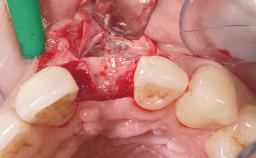

A 42-year-old female patient was referred to our clinic at the School of Dentistry of the University of São Paulo in November 2004, presenting a deficient restoration in the upper left central incisor. The clinical examination revealed no gingival retraction or any signs of gingival inflammation and, therefore, previous periodontal treatment was not considered. The patient presented a high lip line at full smile and a thin tissue biotype. This combination characterized a high-risk situation from an anatomic point of view, which required careful preoperative planning and cautious surgical execution.

Bone Augmentation No

Soft Tissue Grafting None

Placement Protocol Immediate implant placement

Loading Protocol Immediate